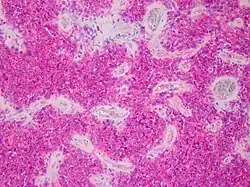

PNET des Zentralnervensystems (ZNS-PNET). Die Erstbeschreibung eines PNET des Zentralnervensystems erfolgte 1973 durch Hart und Earle. Gegenstand ihrer Untersuchungen waren undifferenzierte Tumoren der Großhirnhälften (Hemisphären) oberhalb des Kleinhirndachs (Tentorium cerebelli): diese Beobachtung führte zu der gebräuchlichen Bezeichnung supratentorielle PNET (ST-PNET). Die PNET des Zentralnervensystems weisen auf feingeweblicher (histologischer) Basis deutliche Ähnlichkeiten zu Medulloblastomen, Pinealoblastomen und anderen Tumorarten auf. Einige Untersucher haben diese Ähnlichkeit zum Anlass genommen, die PNET als zusammenfassende Gruppe von embryonalen Tumoren des Zentralnervensystems zu definieren: diese Auffassung ist aber umstritten.

Die richtungsweisende Diagnostik erfolgt zumeist über eine feingewebliche (histologische) Untersuchung nach Probeentnahme (Biopsie) oder Entfernung des PNET (Resektion durch Operation). Letztere kann insbesondere bei PNET im Zentralnervensystem nur teilweise oder gar nicht möglich sein.